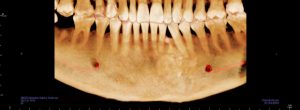

طلب منى اشعة بانوراما عادية علي الفكين و عملتها و تم عرضها علية فعاد و طلب مقطعية للتأكد من شيء موجود تحت الناب الايسر بالفك السفلي و بالفعل عملت المقطعية وتم عرضها علية

وقالي هنتابعها هى حاجة عندك من سنين طويلة يمكن اكتر من ٢٠ سنة و موجودة في اشعات البانوراما القديمة اللي كنت بتعرضها علي دكتور شريف المفتي في ٢٠١١ و ٢٠١٢ رحمة الله علية هى اسمها compound odontoma و حاجة حميدة تماما و لا خوف منها و ممكن تعيش بيها لكن هنتابع حجمها بالمقطعية كل ٦ شهور و متقلقش منها .

قالي انت لو عاوز تعملها اعملهالك و مش عاوز منك فلوس لكن انا بقولك دى مجموعة اسنان زيادة مطلعوش من وانت صغير لان اسنانك كانت كاملة حوالي ٦ او ٧ تحت الناب و حجمهم تقريبا ٢ سم و قولنا نتابعها فقط بالمقطعية مش واثق فيا شوف حد تاني و بالفعل قالي روح لدكتور فولان إنسان محترم و اعرض علية الموضوع عشان ترتاح و ابقي بلغني قالك اية بالفعل روحت و تم عرض كل شيء علية قالي نصا تنساها تماما و تعيش حياتك انا هاخد منك فلوس و اشتغل بس حرام عليا مش محتاجها و كتبلي تقرير قولتلة طيب نتابعها كل ٣ شهور

ولا ٦ شهور عشان ممكن تكبر او تتحول لخبيث قالي مش بتتحول مستحيل و لا تعمل مقطعية تاني و لو عملت بعد سنتين هتلاقي الحجم دا زى ما هو دى حاجة بتكبر ببطىء شديد جدا علي مدار سنين طويلة جدا .

قولت اعمل اشعة بانوراما مع نفسي كدا اطمن علي المشكلة.. لقيت الحجم شكلو متغير عن اللي فاتو بتوع ٢٠١٨ و ٢٠١١

قولتلة طبعا قالي انا هكون موجود هناك غدا بكلية طب الأسنان تعالي و هنعمل مقطعية عندنا و بالفعل روحت قالي اسمع البانوراما دى بايظة و مش هيطلع اي تغير قولتلو لا يا دكتور انا ملاحظ الاشعة و الفرق قالي ماشي يا فندم بينا المقطعية!

و بعد عرض ال cd قومت بالاتصال علية قالي مافيش اي تغير يا نادر زى ماهي و مافيش حاجة تخوفني.